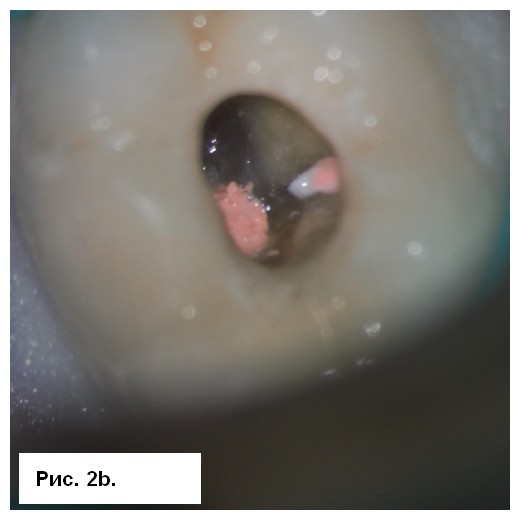

На рентгенограмме (рис. 1а) отмечались большие радиолюсцентые очаги на обоих корнях. Был поставлен диагноз: «некроз пульпы и острый апикальный абсцесс зуба 46». После консультации со стоматологом-ортопедом было принято решение провести эндодонтическое лечение с доступом к корневым каналам через существующую коронку. После вскрытия полости зуба было получено большое количество гнойного отделяемого с кровью (рис. 1b). Дренажу благоприятствовала ирригация 3 % NaOCl (рис. 1с), проведена инструментация корневых каналов системой 2Shape (MICRO-MEGA) и определена рабочая длина (рис. 2.а). Корневые каналы были заполнены гидроксидом кальция.